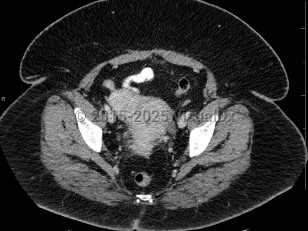

Uterine fibroids

Fibroids are often asymptomatic and may be only first noted incidentally on imaging done for other reasons, but patients can also present with abnormal bleeding, infertility, painful intercourse, constipation, increased pelvic or bladder pressure, urinary frequency, or rectal pressure.

Look For